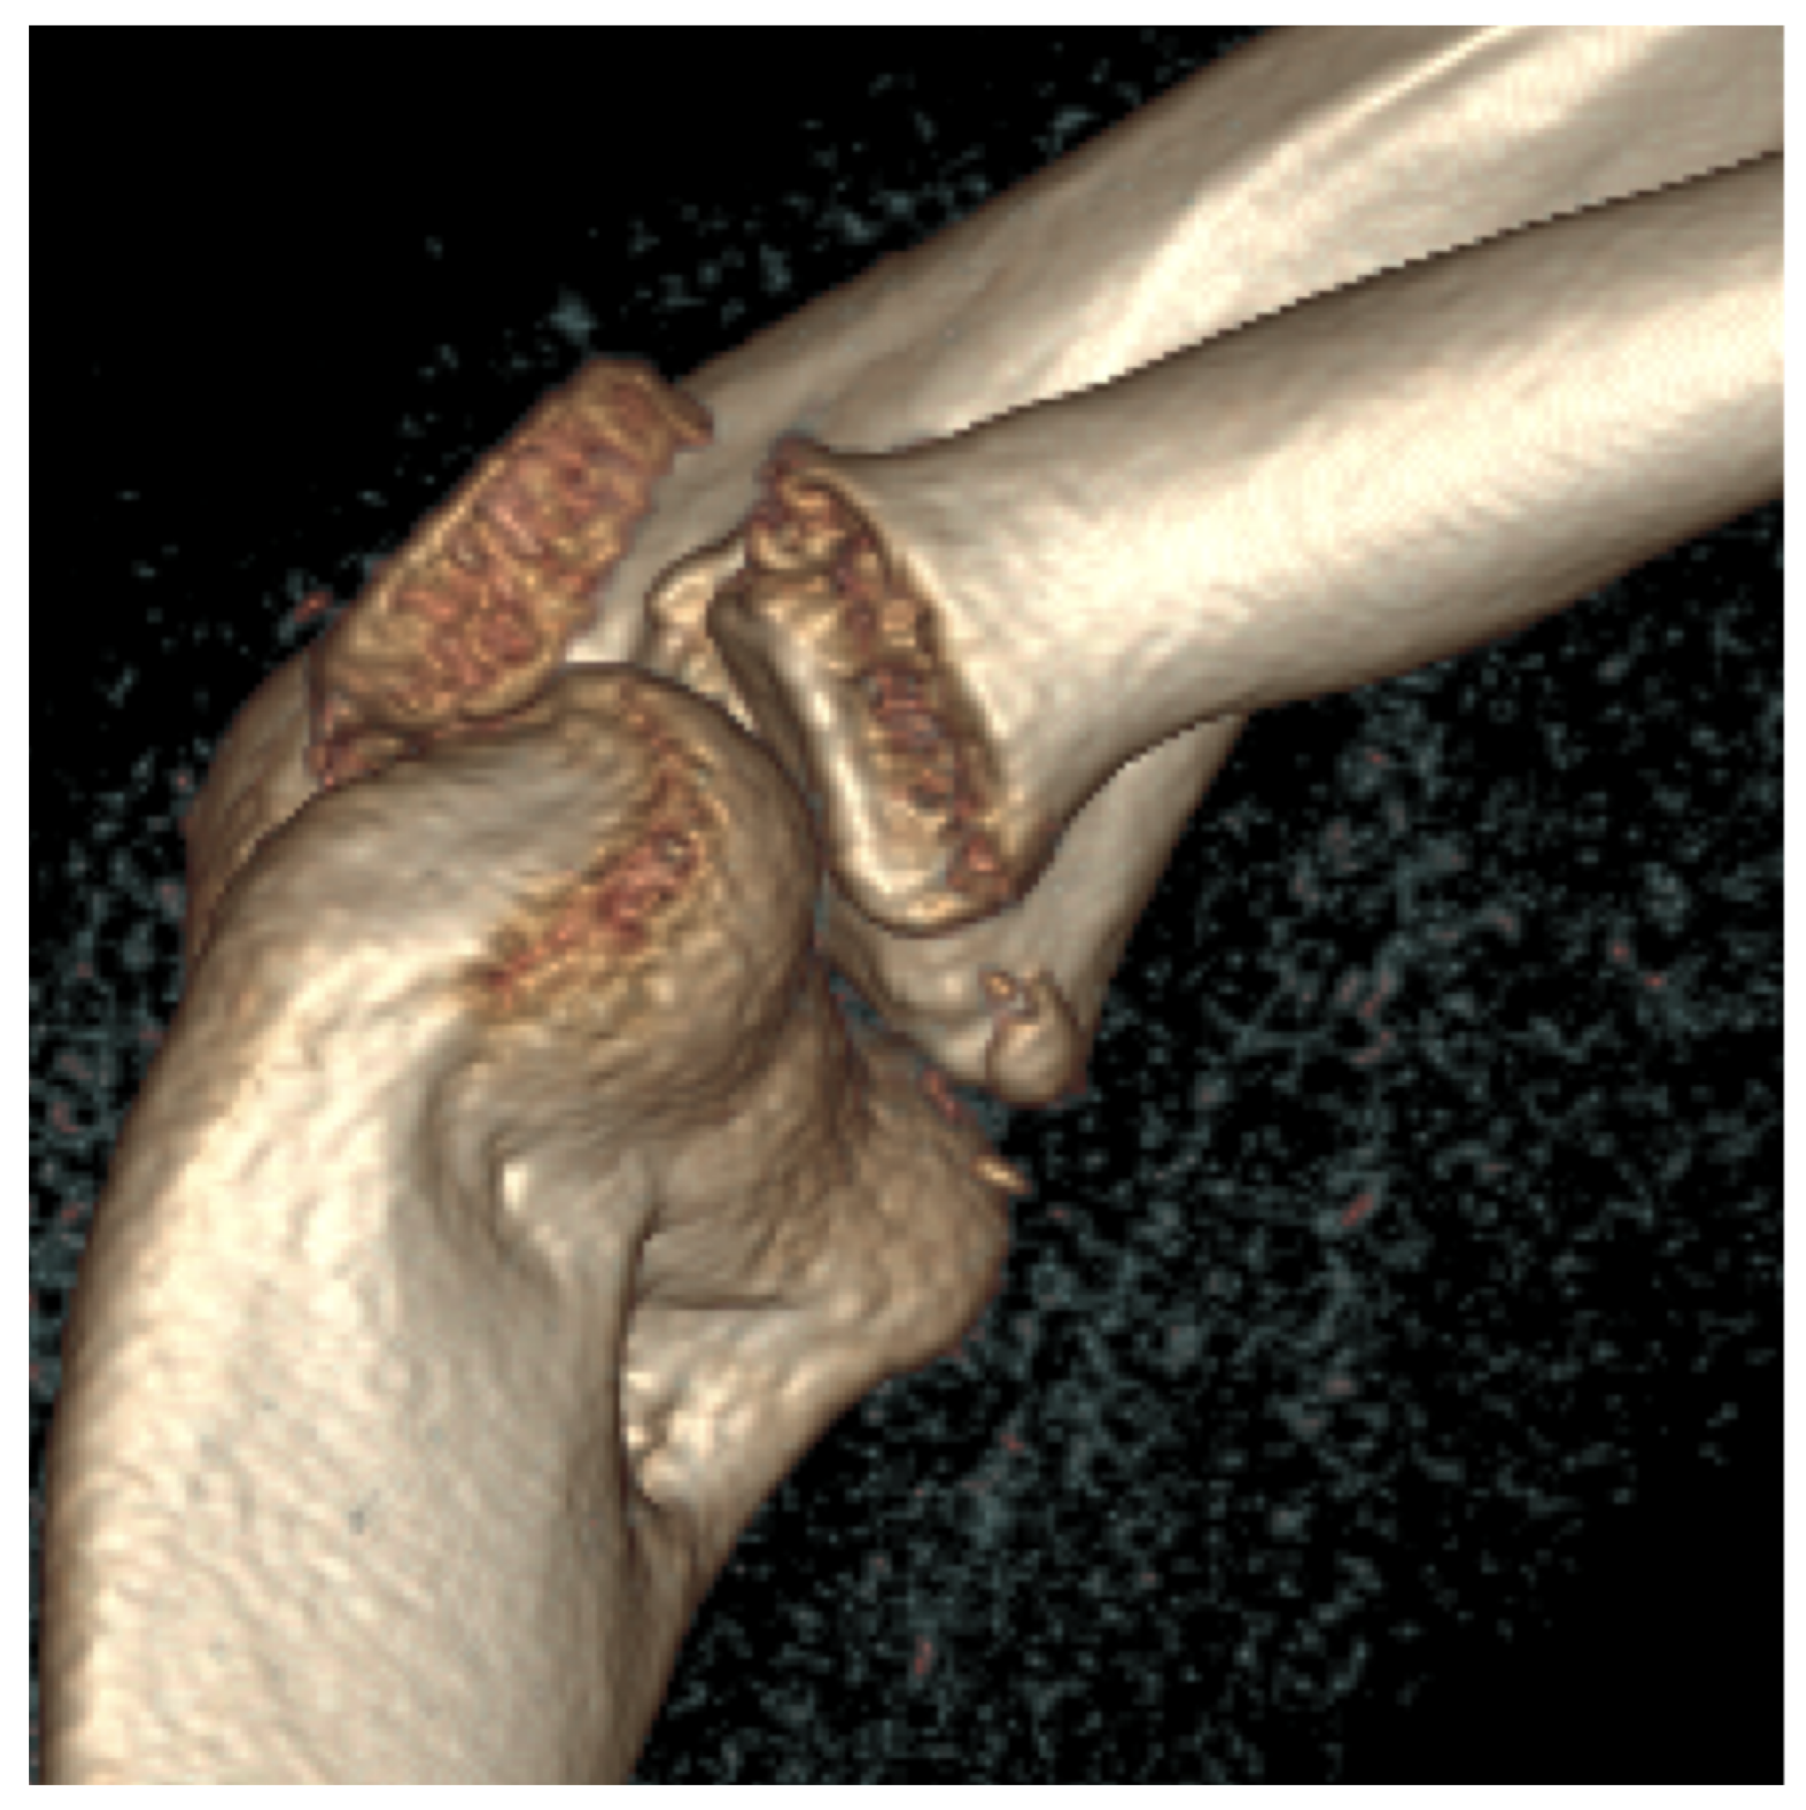

Third patient: A 17-year-old patient was admitted following a snowboarding injury that affected her elbow. Although the patient reported pain and swelling of the proximal forearm was visible upon inspection, the Moberg test was negative. The fracture of the radial head was confirmed by the initial X-ray, after which a CT was performed, which established a Mason type II fracture and dislocation of the radial head (Figure 7).

Figure 7.

The CT images confirm the Mason type II fracture and dislocation of the radial head.